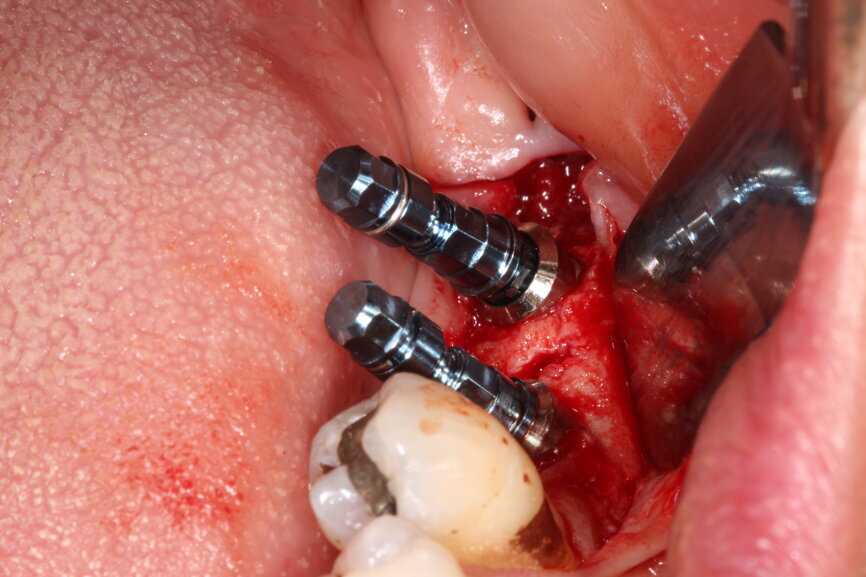

Fig. 9: Surgical placement of LL67 implants.

Even with assisted surgery or guided surgery, there are sometimes certain restrictions that prevent us from achieving the most ideal implant placement, such as this case shown where posterior access in the second molar region was reduced, so achieving the perfect parallel was extremely difficult.

There are fully guided systems available that allow for absolutely precise implant placement, but these are fraught with complexities and should be reserved for experienced clinicians. The accuracy of surgical guides should not be used to make up for a lack of surgical competency however.

There are many factors to be considered when using surgical guides, including whether the guide is tooth-, soft tissue- or bone-supported. Tooth-supported allows the greatest degree of accuracy.